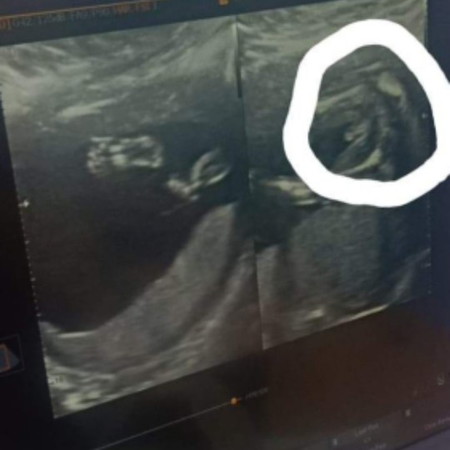

แม่ๆคนไหนรู้เพศน้องแล้วบ้างคะแล้วรู้ตอนกี่w.คะ ( บ้านนี้รู้ตอน17w.ค่ะ )

บ้านนี้ผญค่า พอดีต้องตรวจ Nifty